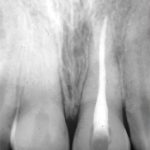

Reimpianto post traumatico di incisivo centrale superiore dopo trattamento endodontico extraorale e stabilizzazione con legatura chirurgica. Analisi retrospettiva a 23 anni